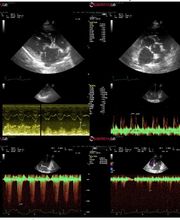

Medicina General. Cirugía. Análisis clínicos. Diagnóstico por imagen (ecografía, radiología, ecocardiografía). Traumatología. Endoscopia. ESPECIALISTAS en distintas disciplinas: Dermatología, Homeopatía y Medicina Felina.